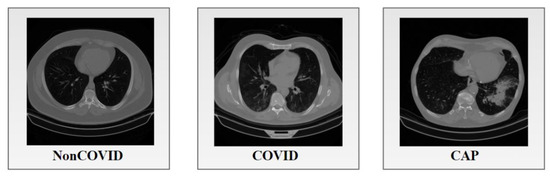

2.4. Anatomical Features of Lung CT Scans

A CT scan contains information regarding the airways and blood vessels which can yield essential information for diagnosis, e.g., the diameter of arteries and bronchi and the extent of wall thickening. For an automated and reliable measurement system of these changes, knowledge regarding the anatomical structures visible in a CT scan is crucial. Prior studies have not taken bronchi-artery alterations into account. As this research attempts to consider these alterations in classifying lung diseases, it is important to understand the anatomical features of lung CT scans. Figure 2 shows the anatomical structures of a lung CT scan.

Figure 2. Anatomical structures in a lung CT scan.

The human body has two lungs, with the mediastinum between them. These can be seen in a CT scan. Both lungs contain veins, arteries, and BA pairs. The lungs are subdivided into lobes, where the left lung comprises two distinct lobes, the upper and the lower lobes, and the right lung part has three lobes, the upper, middle, and lower lobes. The airway tree is called the bronchial tree. The starting point or first branch of the tree is the trachea. The trachea is divided into two prominent bronchi leading to the left lung and the right lung. These two main bronchi are then subdivided into several smaller bronchi. The airways comprise lumen and airway walls where the lumen is normally filled with air. Moreover, two vascular trees are found, the arterial and venous tree, where the arterial tree is responsible for supplying blood to the lungs, and the veins are responsible for draining blood from the lungs. The veins and arteries have similar intensity levels in CT images. One important aspect is that arteries are usually observed to be adjacent to the bronchi, whereas the veins typically do not run alongside the bronchi.